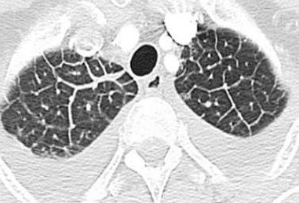

Patrón reticular / intersticial IMAGEN TC

Morfología poligonal